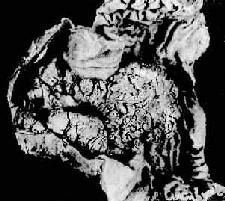

3.浸润型(infiltrating type)组织向胃壁内呈局限或弥漫浸润,与周围正常组织无明显边界。当弥漫浸润时致胃壁增厚、变硬,胃腔缩小,粘膜皱襞大部消失。典型的弥漫浸润型胃其胃状似皮革制成的囊袋,因而有革囊胃之称(linitis plastica)(图10-16)。

图10-16 弥漫浸润型胃

胃壁因组织的弥漫浸润而显著增厚